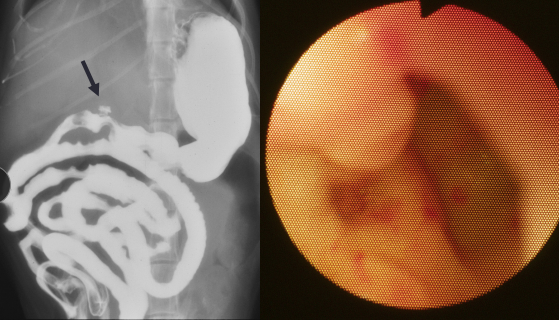

Intestinal Adenocarcinoma

Most common primary neoplasm of GI tract

Dogs

CS: vomiting if causing obstruction; weight loss,

diarrhea

diffuse thickening or focal, circumferential mass

lesions

Dt: contrast radiographs, explore sx

Apple core lesions w/ contrast = focal

Tx: surgery, good prognosis if fully resected